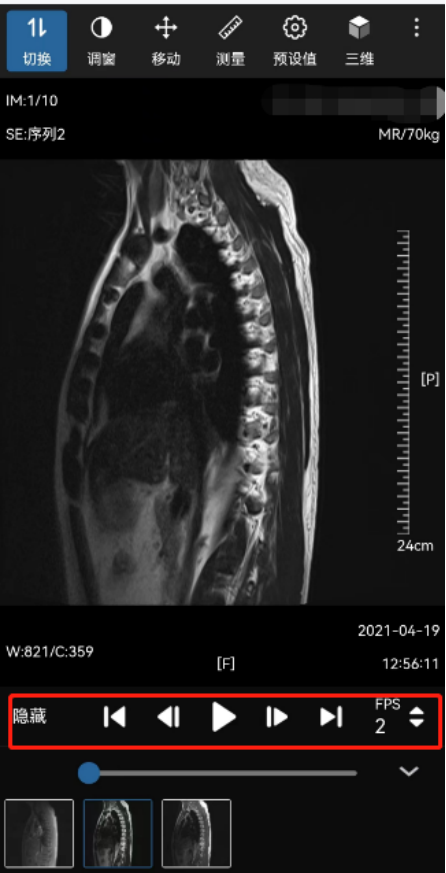

4.打开“查看图像”界面,下方有多种功能